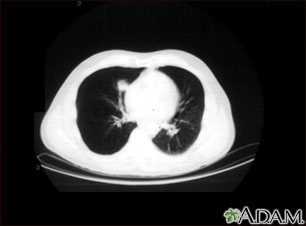

Lung nodule, right lower lung - CT scan

A CT scan showing a mass in right lower chest near the heart (left side of photograph).